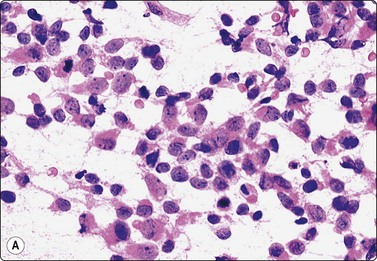

image

Fig. 13.8 Poorly-differentiated adenocarcinoma

Poorly cohesive malignant cells with large vesicular malignant nuclei and large nucleoli. Note small sheet of benign epithelium on right in A (A, DQ; B, Pap, HP).

Poorly-differentiated carcinoma (Fig. 13.8)

Malignant irregular three-dimensional clusters and numerous dissociated cells,

Obvious increase of N : C ratio,

Large nuclei and nucleoli,

Intense hyperchromasia,

Rare or absent microacini with frank atypia,

Dispersed cells or naked nuclei may dominate the smear. Nuclei may be smudged. Caveat: do not mistake for high-grade lymphoma.

In smears of prostatic carcinoma, sheets of benign glandular epithelial cells are commonly seen side-by-side with aggregates of malignant cells (Fig. 13.6), reflecting the diffusely infiltrative growth of the tumor. Benign and malignant cells can be directly compared (very helpful clue) and differences in cytoarchitectural features are easily appreciated. Nuclear enlargement is one of the most important criteria of malignancy. Nucleolar enlargement is better demonstrated in Pap-stained smears.

Absence of visible cell membranes, nuclear crowding and overlapping and dissociation of cells are other important criteria. The presence of coarse intracytoplasmic secretory granules makes malignancy unlikely, but they can occasionally be found in cells from well-differentiated adenocarcinoma. Cytoplasmic vacuolation may be seen in both benign and malignant cells. Nuclear pleomorphism and chromatin abnormalities are obvious in less well-differentiated cancers but may be subtle in well-differentiated carcinomas, rendering a definitive malignant diagnosis difficult (Fig. 13.5). Demonstration of basal epithelial cells by immunocytochemistry may be of help in the distinction between well-differentiated adenocarcinoma and adenosis or basal cell hyperplasia,5 but interpretation is more difficult than in histologic sections. Immunostaining is a useful tool for the diagnosis of prostate cancer at metastatic sites.42 Results may be conflicting in metastases of poorly differentiated carcinomas.